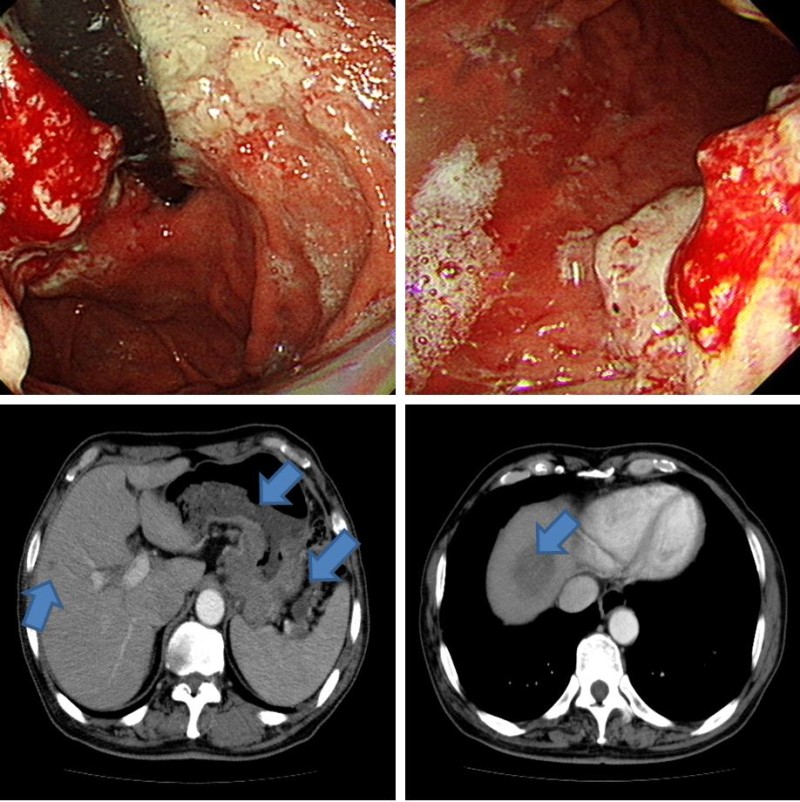

위암이 개괄적으로 병에 걸려해보았을 때 발생할 수 있는 증상입니다. 암의 부피가 증가함에 따라 혈관을 압박해서 깨진 혈관에서 혈액이 흘러나와 대변처럼 배출되며 검은색 혈변을 볼 수 있다고 합니다. 대변에 있는 피를 생각할 때 우리는 그것이 붉을 것이라고 고려되지만 다른 형태를 취할 수 있다하는 것을 알려져 있으며 대변에 피가 있다라고 하면 위암이 아니더라도 확연히 이상이 있는 것입니다.

위암 초기증상 7. 혈변

위암은 소화계에 출혈을 일으키기 때문에 대변에 혈액이 섞여 나올 수 있어요. 피 색상은 선홍색이나 더 진한 컬러을 드러내며, 복통이나 변비, 설사 같은 다른 배변 증상이 같이 오기도 해요.

구역질과 구토는 위와 십이지장 사이의 경계인 유문부 폐색에 의해 가끔가다 잘 볼 수 있으며 진행암에서는 부위에 무관히 출현하는 증상이죠. 위암 초기증상보다는 진행성 위암일 때 많이 나타나요.

위암 생존율